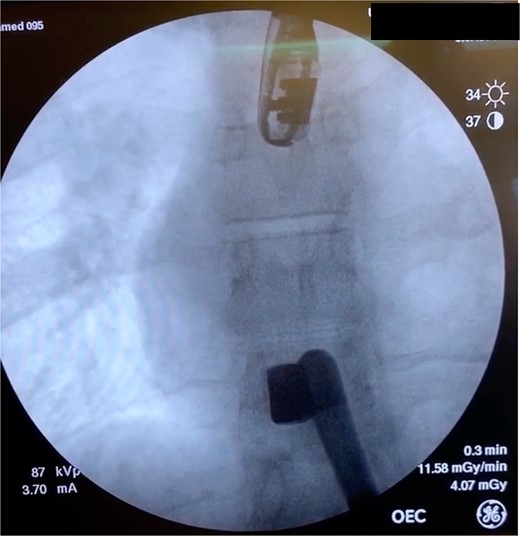

In the OR, exploratory laparotomy, right nephrectomy, liver packing, and pericardial window were performed. The pericardial window was negative for blood. With no suspected cardiac injury, intraoperative fluoroscopy (Fig. 1) and transesophageal echocardiogram (TEE) (Fig. 2) were used to locate the bullet. It was suspected to be intravascular secondary to venous embolism from the retro-hepatic inferior vena cava (IVC). Cardiothoracic surgery was consulted for removal of the bullet. With abdominal hemorrhage controlled, the surgeons agreed the patient was an acceptable risk for anticoagulation and cardiopulmonary bypass. Sternotomy was performed, the patient was placed on cardiopulmonary bypass, and the bullet was removed through a right atriotomy.

Intraoperative fluoroscopy demonstrating bullet in the right ventricle.

Case 1 involved a stable patient with a single GSW to the left back and a retained bullet over the right ventricle. The trauma team identified the bullet overlying the cardiac silhouette and performed a CT scan to determine its trajectory. The scatter artifact complicated localization, but a pericardial window excluded cardiac injury. Intraoperative imaging (fluoroscopy and TEE) revealed a venous bullet embolism from the retro-hepatic IVC to the right ventricle. The bullet was mobile on fluoroscopy, and TEE provided the best imaging. The trauma and cardiothoracic surgeons discussed bullet removal timing, considering the patient’s stability and heparinization needs. They opted for immediate removal due to the potential lethality of pulmonary artery embolism. The operation was successful, requiring only one surgery for definitive management. This case highlights the success of immediate bullet removal in hemodynamically stable, asymptomatic patients with venous embolism.